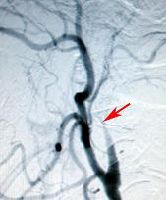

頻繁に右半身の一過性片麻痺(脳虚血発作)を繰り返した左内頚動脈閉塞症例

将来的に大きな脳梗塞の発症が危惧されたため、頭皮の血管を脳の血管につないで血液を補給するバイパス手術 EC-IC bypass)を施行しました。術後、吻合した血管が脳に血流を送っていることが確認されました(矢印)。